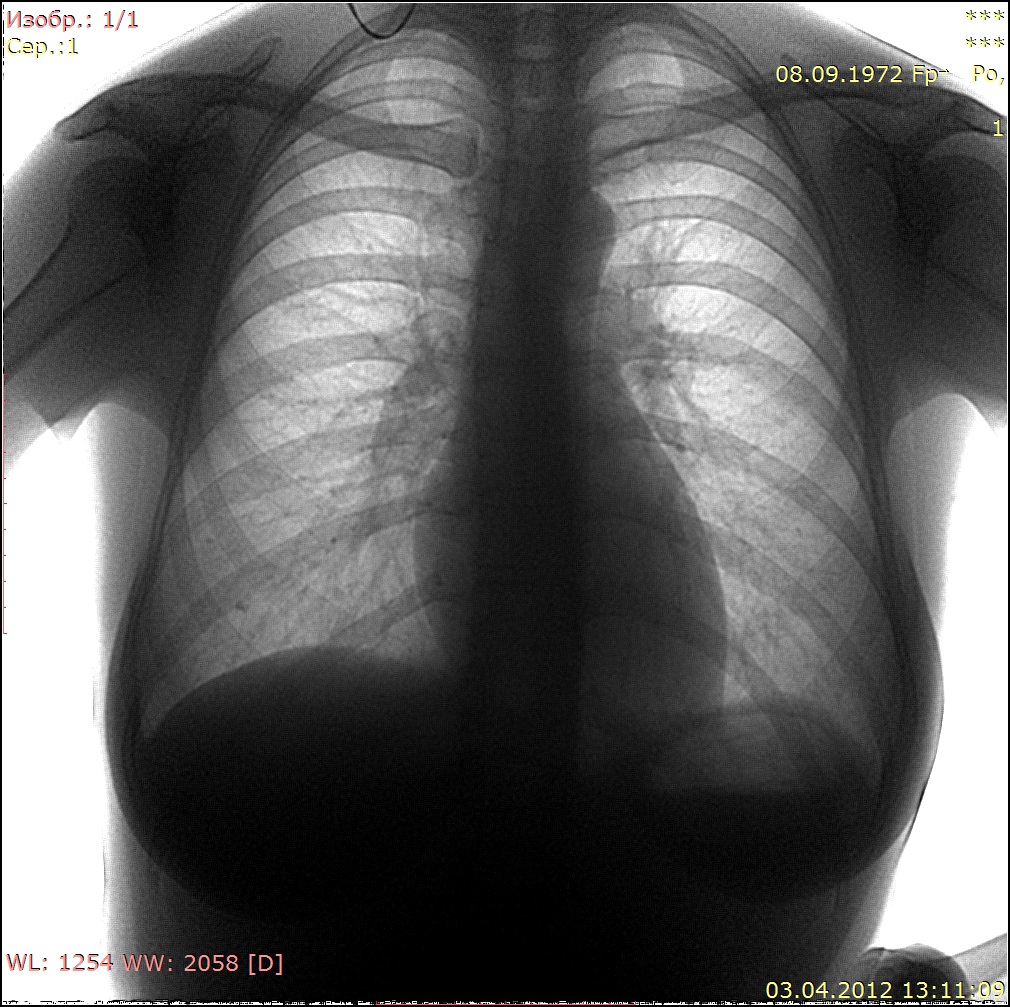

На архивных снимках этой тени нет.

Пересняли

Теперь ничего криминального не вижу. Пусть живёт долго и счастливо!

Норма.

Все равно кажется тонкостенная воздушная полость есть-но тут глубокое ИМХО.Сосудистый рисунок, видимо. Но на боковой тоже есть.Очень ИМХО. Но и с этим можно жить долго и счастливо.Не будем придираться.

На втором снимке, в отличие от первого, задний отрезок 4-го ребра справа расположен выше ключицы, а на первом снимке - на ключице. На втором снимке наружные синусы больше прикрыты тенями молочных желез, на первом снимке - меньше. Значит центральный луч при съёмке во втором случае располагался выше, чем в первом случае, и видимая на первом снимке тень на втором сместилась книзу. Потеряла четкость, располагается там же, на 6-м ребре, но ниже. И все равно линия сосудистого рисунка здесь как бы замыкает овал.